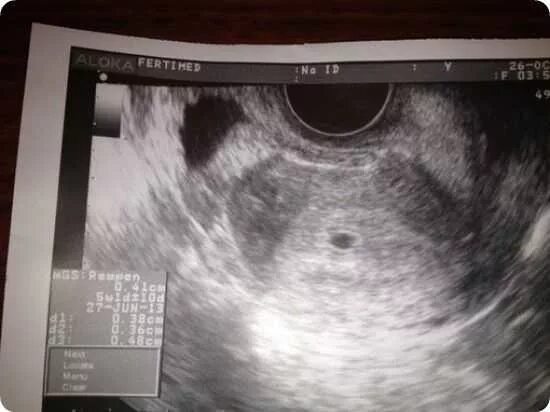

Беременность 1 неделя